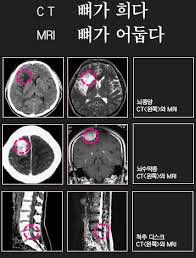

- CT(Computed Tomography): X선을 여러 각도에서 쏜 뒤 컴퓨터로 재구성해 단면 영상을 얻는 검사입니다. 쉽게 말해 고성능 X-ray를 360도에서 찍고 컴퓨터가 합쳐주는 방식입니다.

- MRI(Magnetic Resonance Imaging): 강력한 자기장과 전파를 이용해 인체의 수소 원자 반응을 영상화하는 방식입니다. 방사선을 사용하지 않고 자기장을 이용한다는 점이 CT와 큰 차이입니다.

- CT: 폐, 간, 신장, 뼈처럼 구조가 뚜렷하고 밀도 차이가 큰 장기를 잘 보여줍니다. 특히 교통사고 외상, 뇌출혈, 폐렴, 암 전이 확인 등에 널리 쓰입니다.

- MRI: 뇌, 척수, 근육, 인대, 연골처럼 연부조직(soft tissue)을 정밀하게 볼 수 있습니다. 뇌종양, 허리디스크, 무릎 인대 손상 같은 경우 MRI가 필수적입니다.